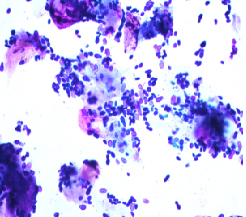

Skin cytology & checking for mites

Aspirates of skin masses